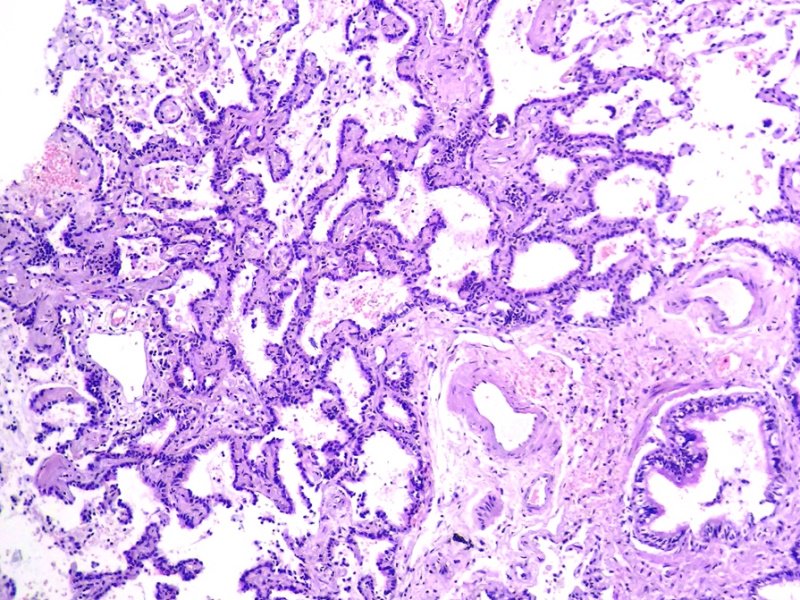

Pulmón. Hiperplasia adenomatosa atípica.